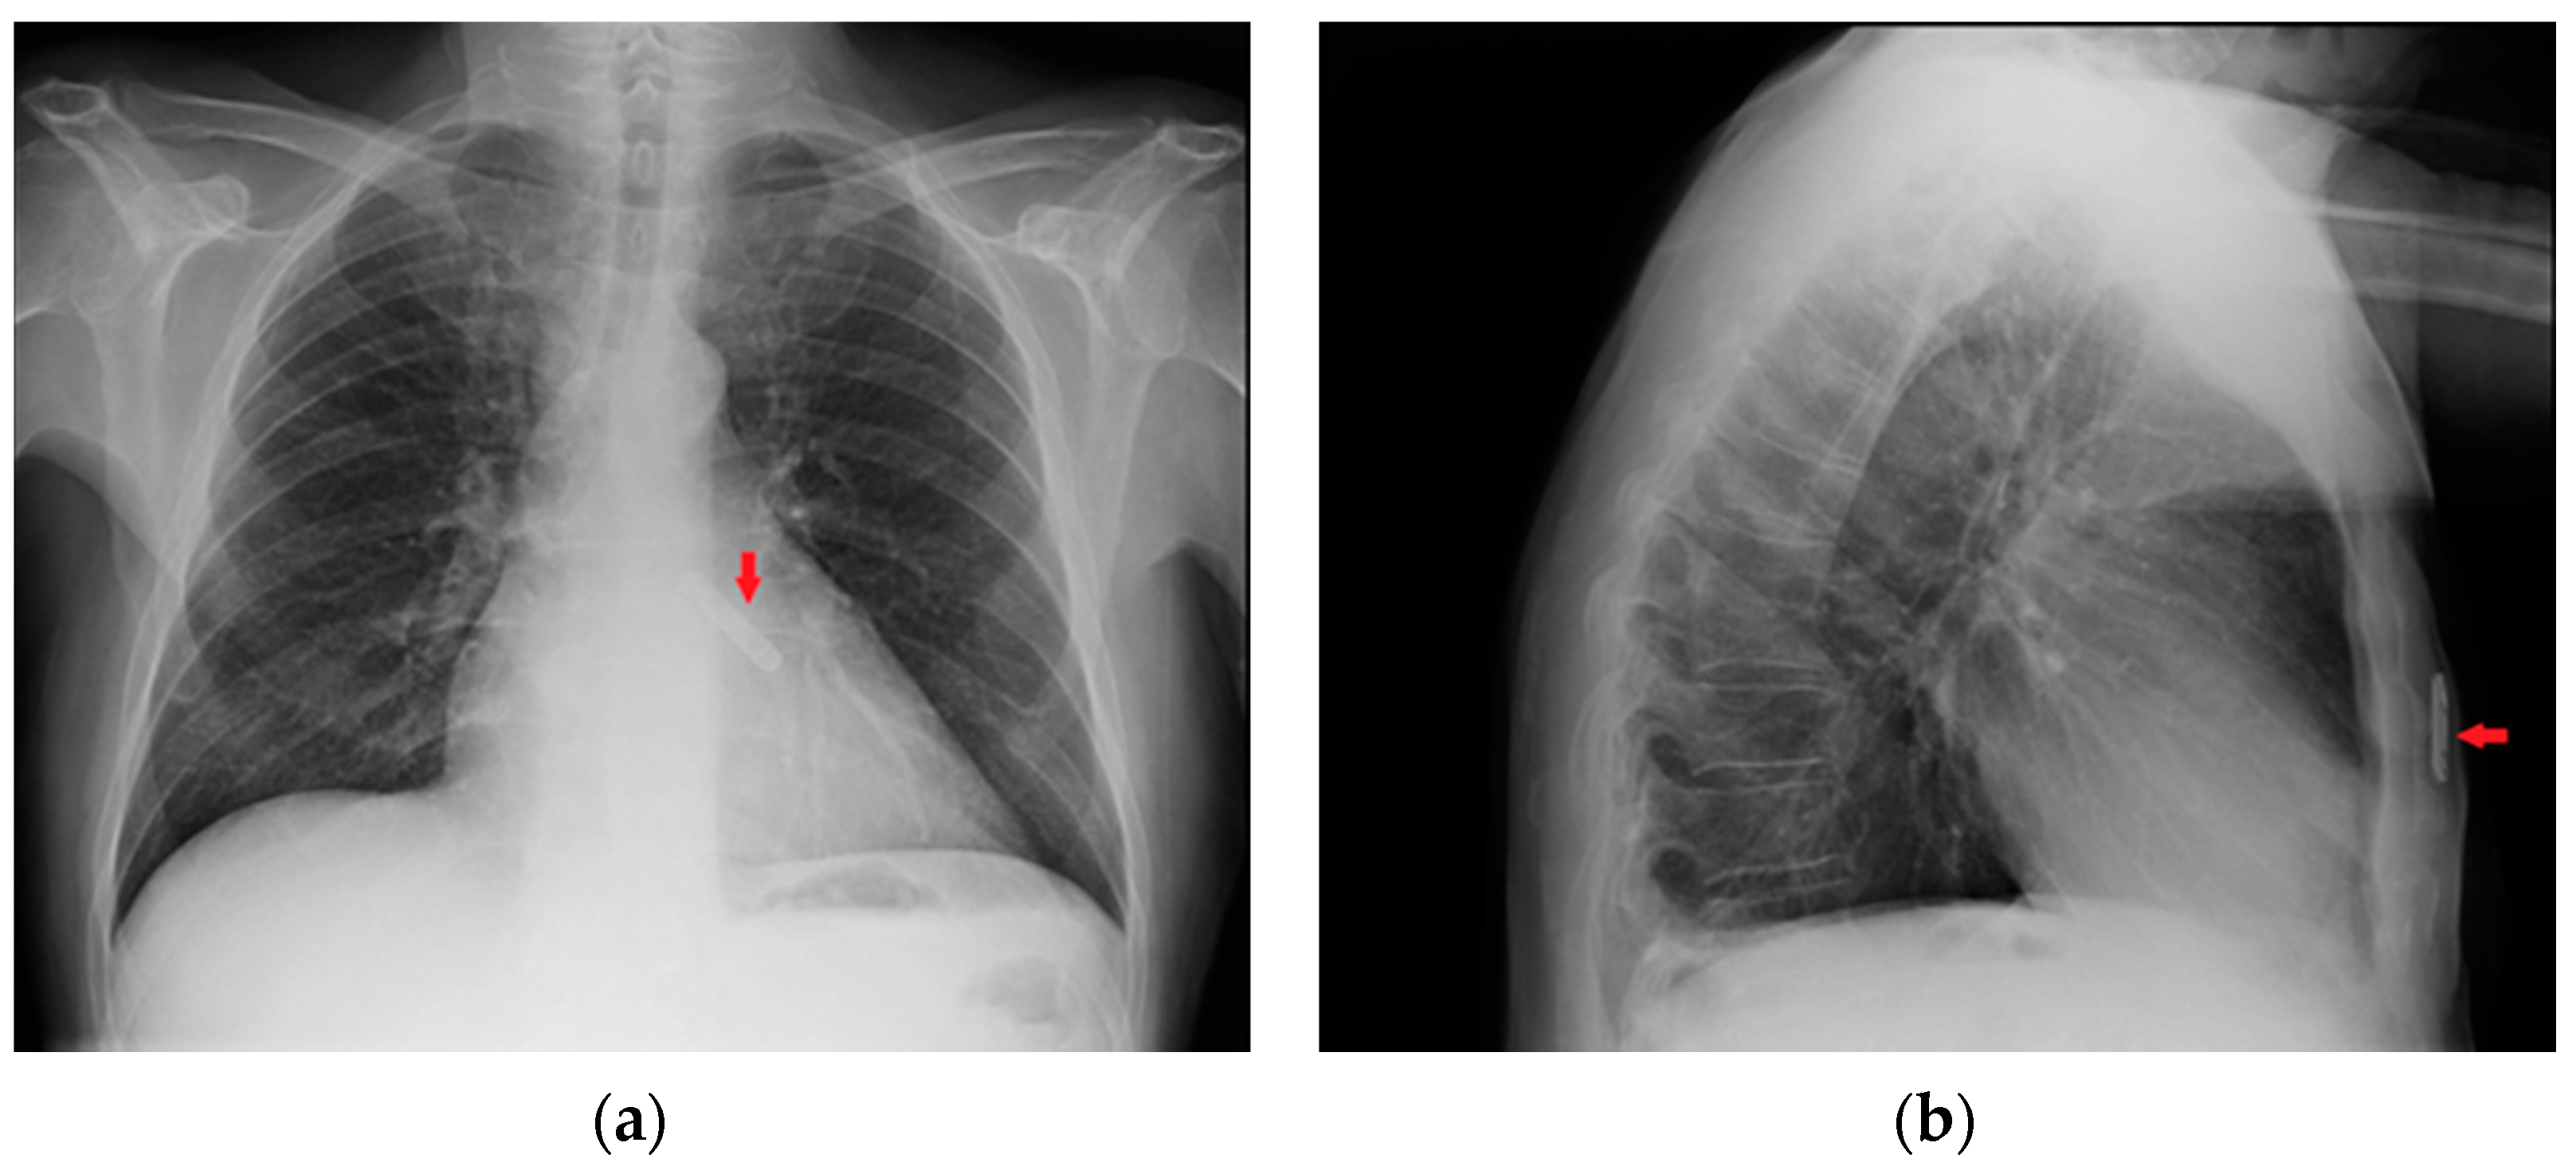

A loop recorder is a long-term hearth rhythm monitor that is usually seen in a CXR as a small radiopaque device with no catheters or electro stimulator wires against the mediastinum (Figure 13). It is located in the subcutaneous tissues and should not cause any CXR-diagnosable complications (the migration of the loop recorder along the chest wall is anecdotical) [20,21]

Figure 13.

Images of a subcutaneous implantable loop recorder on PA (a) and LL (b) views of a CXR (red arrows).